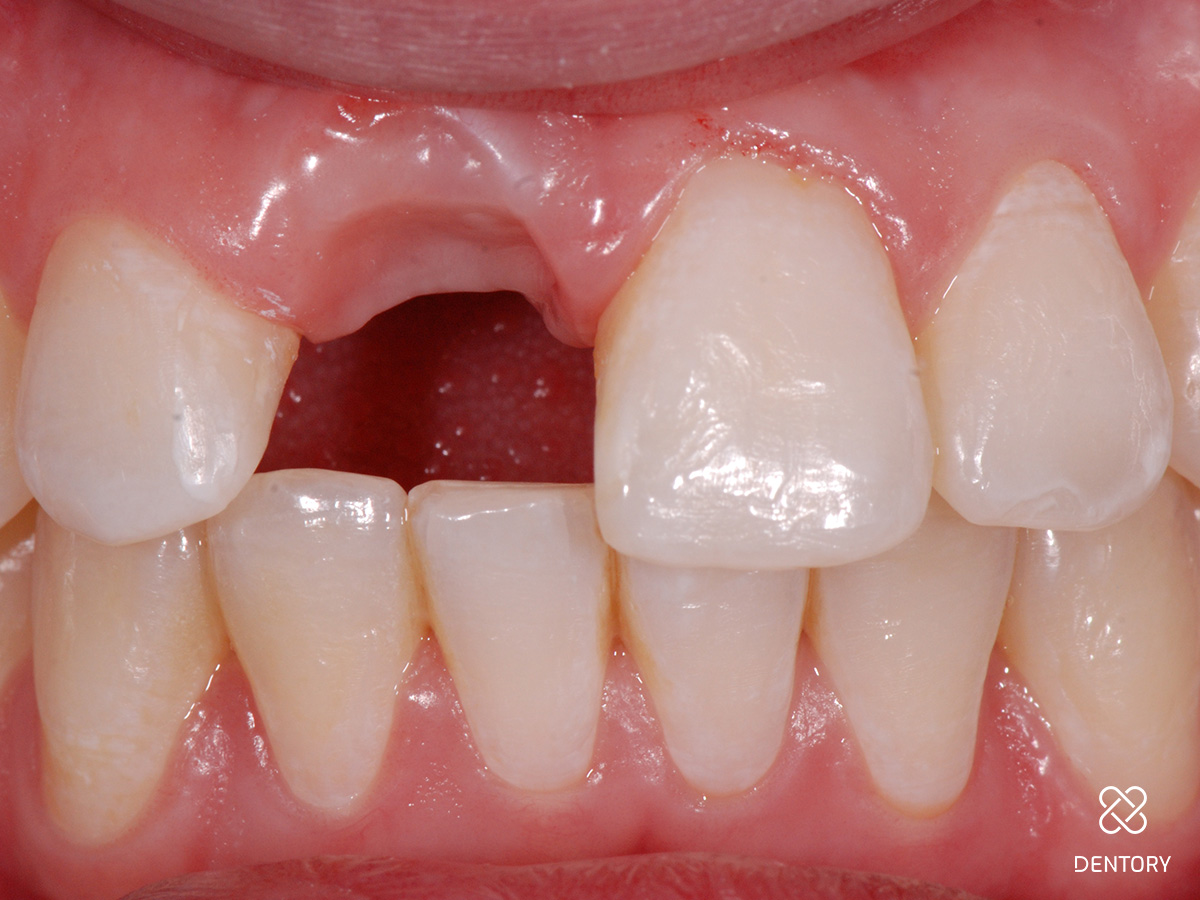

Abbildung 1

Ausgangssituation: Nicht erhaltungswürdiger Zahn 11 aufgrund einer externen Resorption.